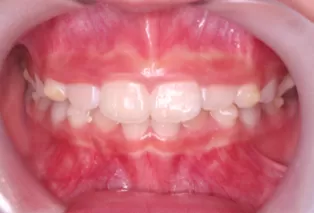

Intraoral photos